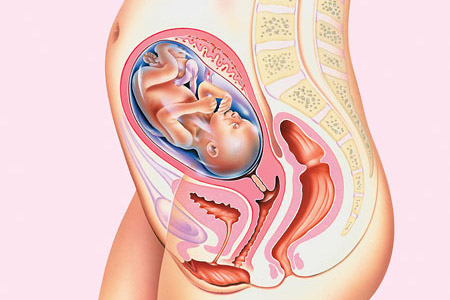

Guida gravidanza: settimo mese

Per la rubrica Guida gravidanza oggi vedremo il settimo mese di gravidanza è quello che va da 26+3 a 30+4 settimane: con il settimo mese inizia anche l’ultimo trimestre di gravidanza.

SETTIMO MESE: COSA FARE

Se non avete ancora fatto acquisti per il piccolo questo è il momento giusto; è importante sia per la mamma che per la coppia restare calmi. Immagino che se siete alla prima gravidanza potrebbe essere difficile: ricordatevi sempre che per tutti i nove mesi (e anche dopo) potete sempre rivolgervi al ginecologo, ad un’ostetrica anche per dei piccoli dubbi.